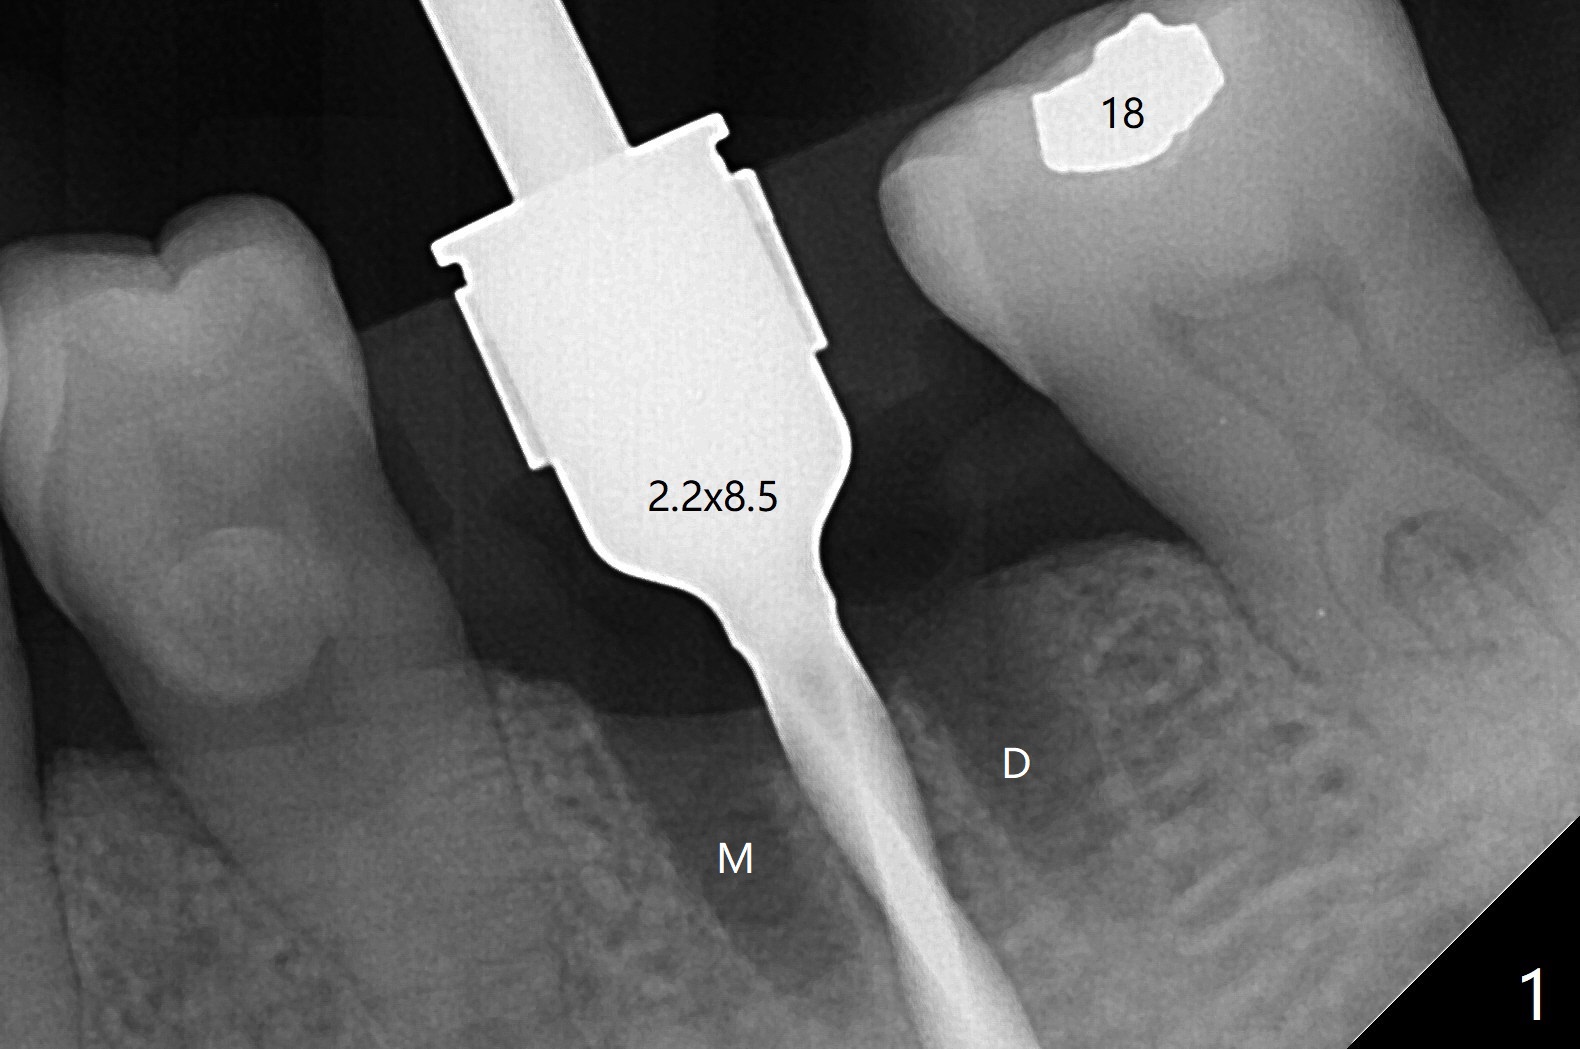

左下第一磨牙拔除后,放置导板,最细钻头到深度,没有偏移: 在中隔正中(图一),细短植体植入后基本保持在中隔之中(图二),扭力~30Ncm,在近中,远中剩余牙槽窝植骨后(图二:*),安置修复基台。制作临时牙冠后,在基台周围再次放置骨粉(图三)。术后7天牙周敷料脱落,12天复查时,临时牙冠周围软组织(角化龈,龈乳头)正常(图四)。